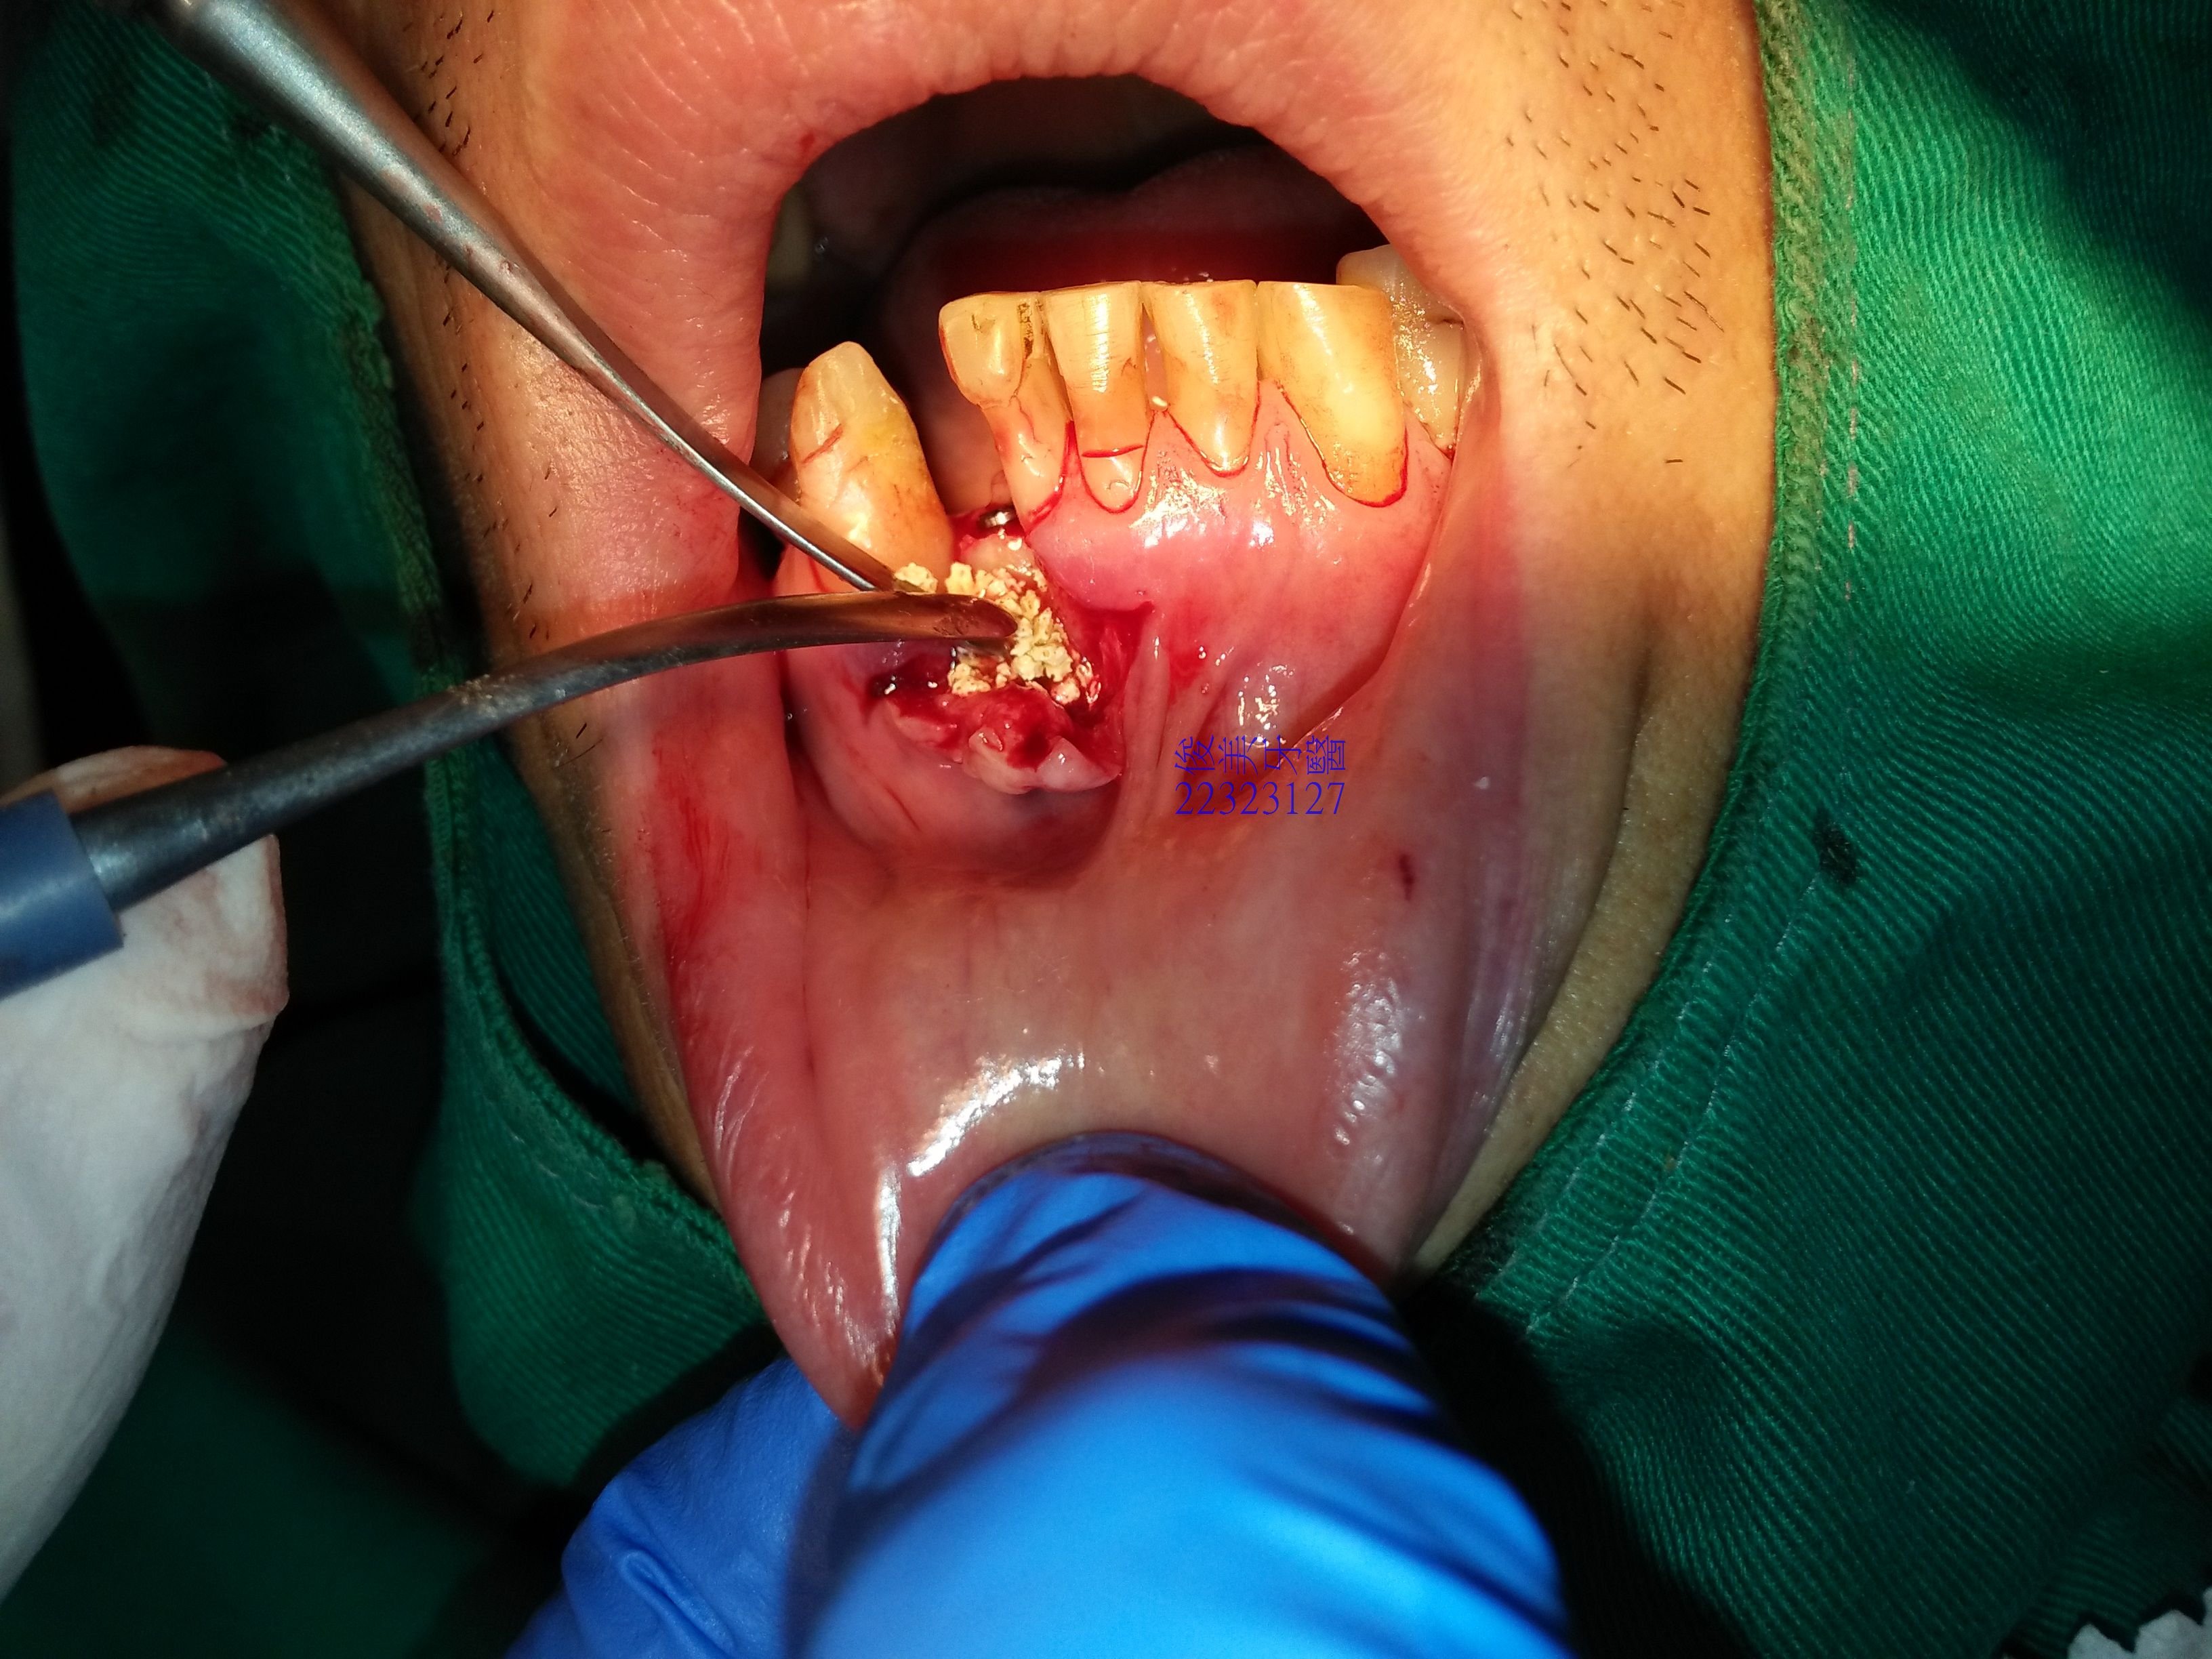

從下顎智齒區取下骨塊,再移植至前牙區,利用特殊骨釘固定,讓自體骨塊癒合、生長。

空隙再用人工骨粉填紮實,希望骨細胞可以生長的更多、更厚。